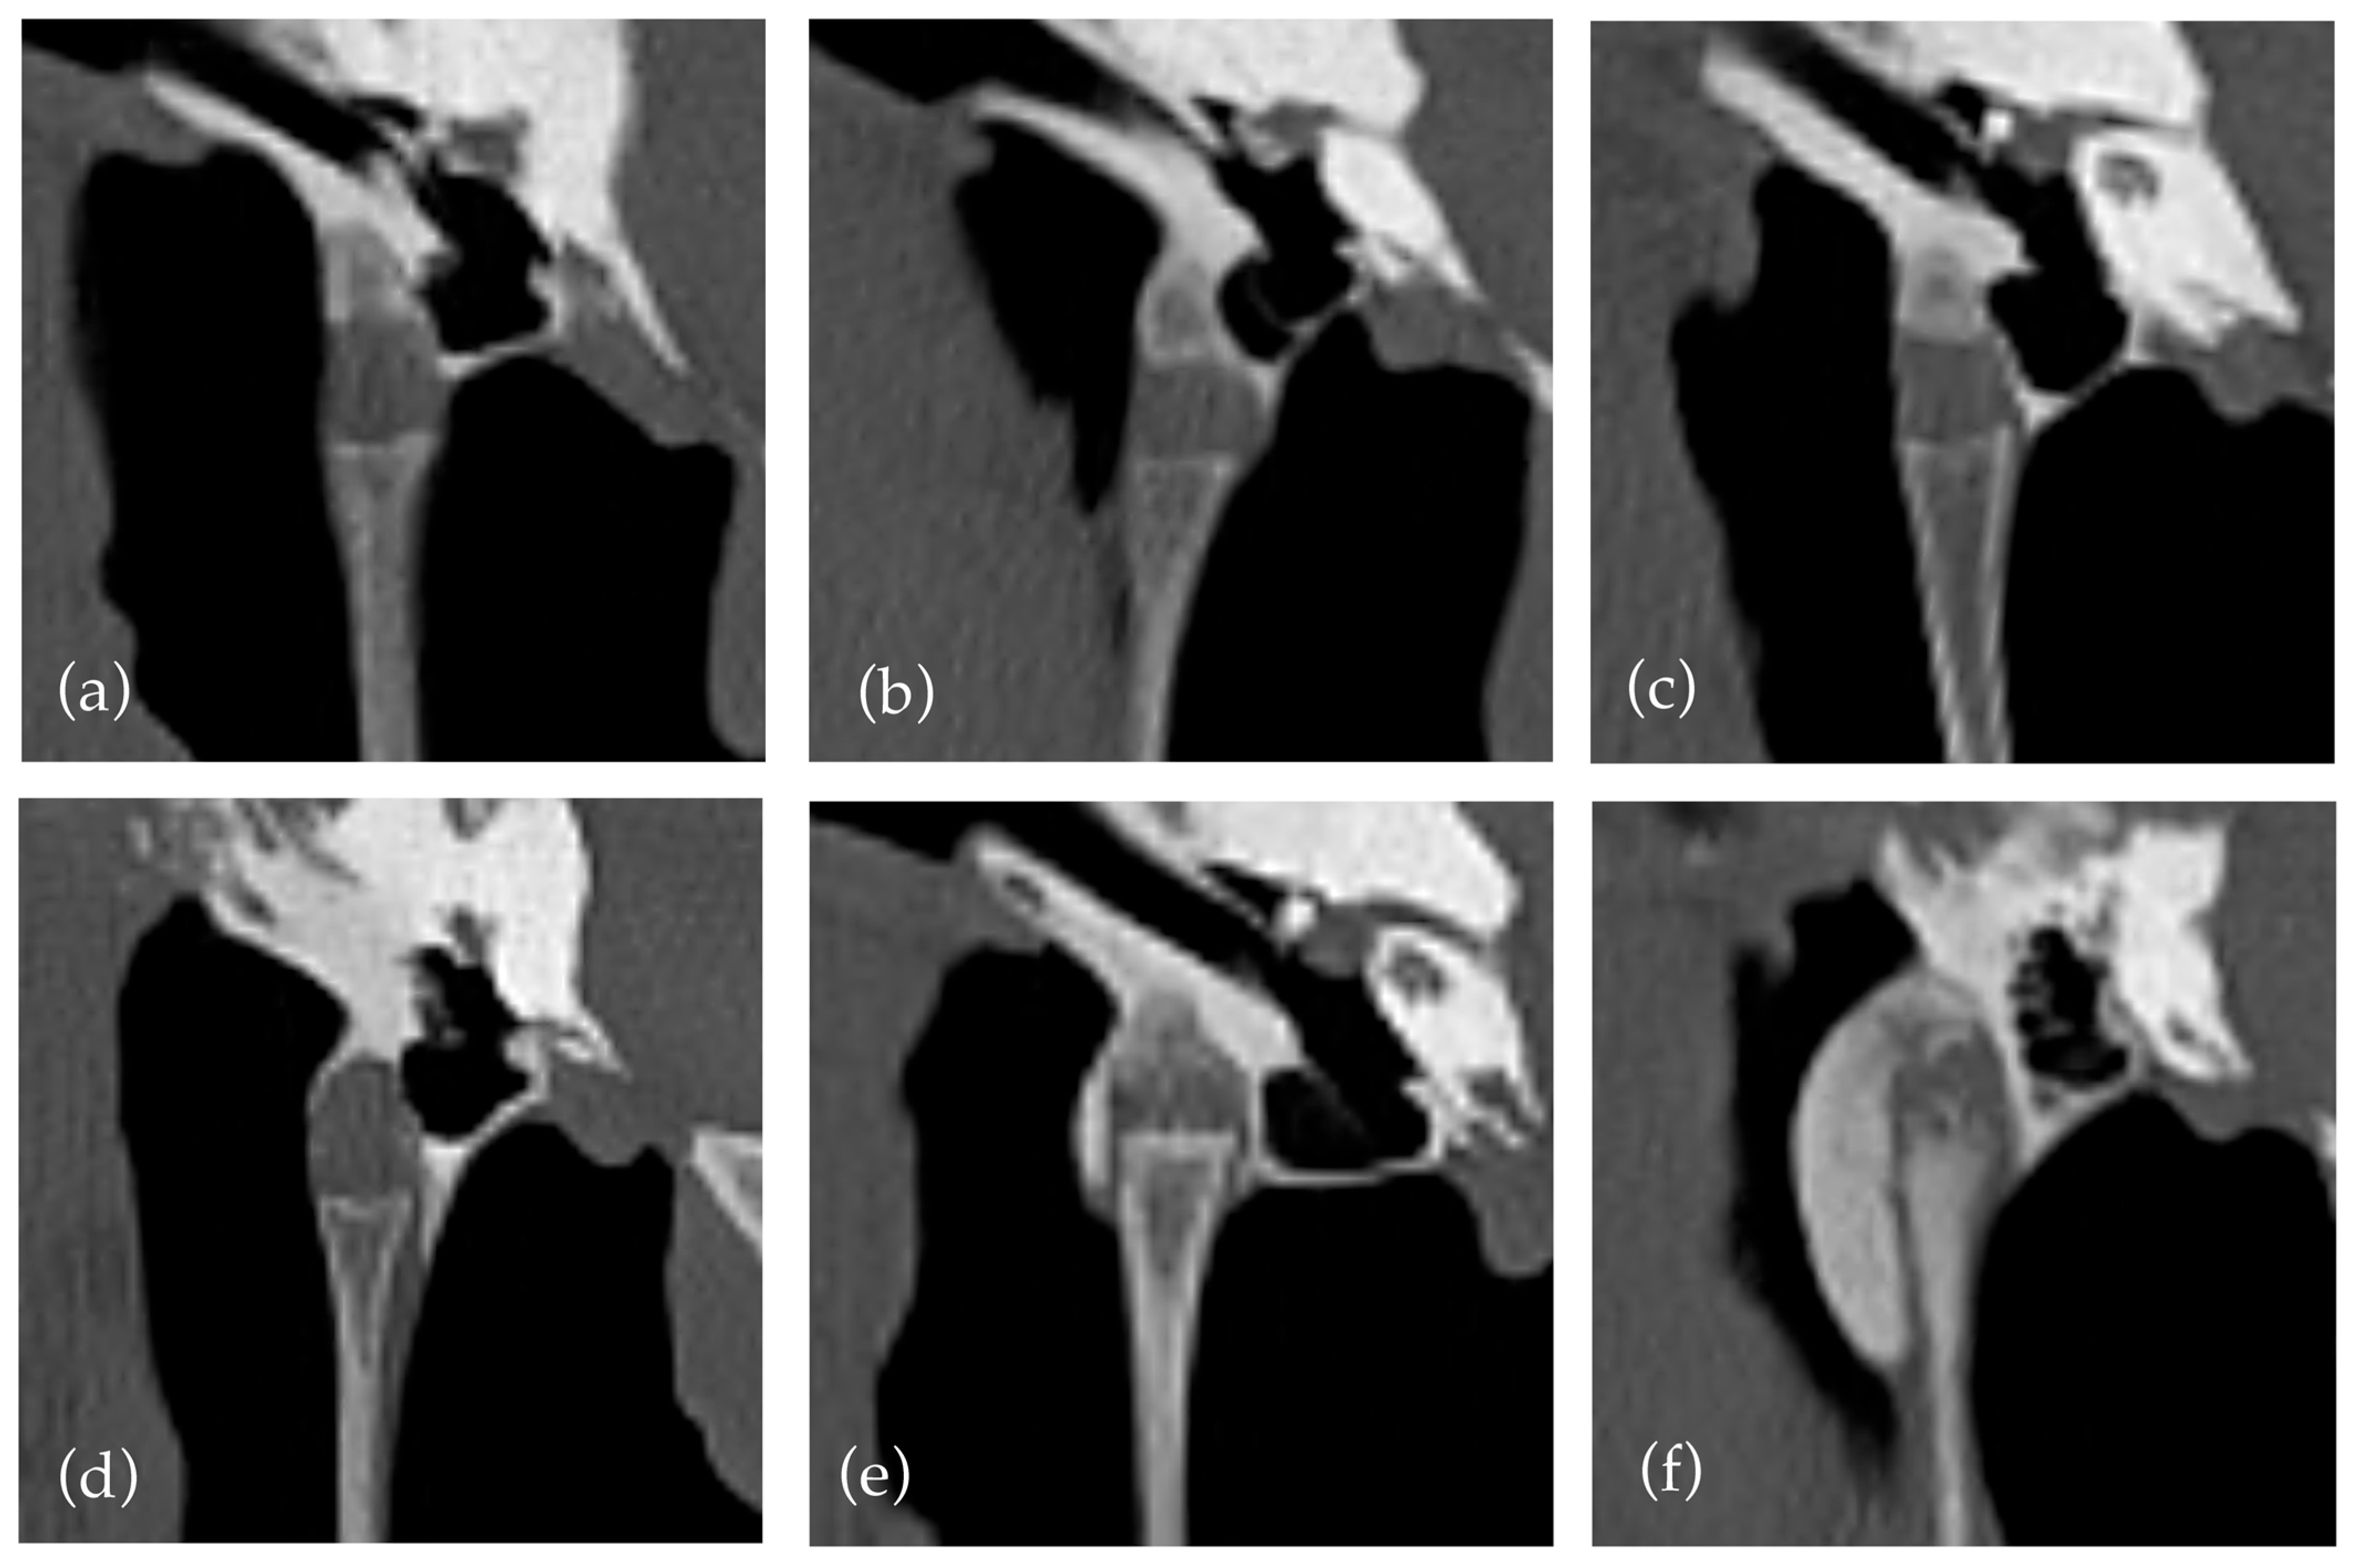

However, the assessment of both features was subjective and challenging due to the influence of multiple factors, not accounted for in the study design. For example, subjective widening of the temporohyoid joint was observed in many horses with proliferative mineralisation of the synovial sheath and in horses with a widened or ‘club shaped’ joint in absence of other factors (Figure 2). Similarly, a narrowing or decrease in height of the temporohyoid joint can be due to a regular reduced height of the tympanohyoid cartilage or irregular ossification of the cartilage, so classification could be challenging.

Figure 2. Illustrations of additional changes of the temporohyoid joint. (a) Mineralisation and narrowing. (b) Widened joint and mineralisation. (c) Widening, narrowing, and mineralisation.